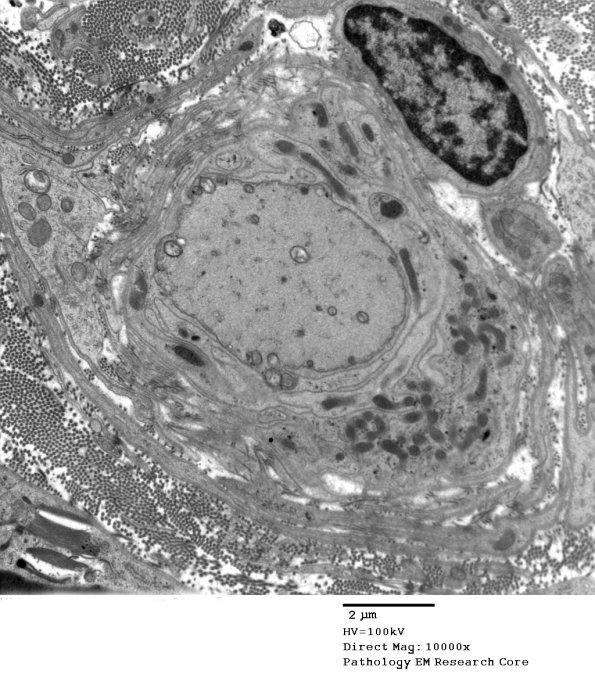

Washington University Experience | PERIPHERAL NEUROPATHY | 7B CIDP | 13C6 Case 13_063 - Copy

Multiple examples of demyelinated large axons, many surrounded by numerous delicate macrophage processes. (electron micrographs)